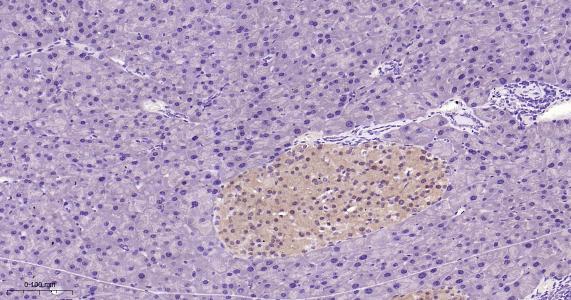

Paraformaldehyde-fixed, paraffin embedded Mouse Pancreas; Antigen retrieval by boiling in sodium citrate buffer (pH6.0) for 15 min; Antibody incubation with TXNRD1 Monoclonal Antibody, Unconjugated(bsm-61558R) at 1:200 overnight at 4°C, followed by conjugation to the bs-0295G-HRP and DAB (C-0010) staining.